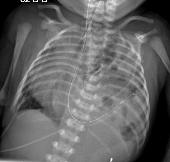

Imaging

A two view abdominal radiograph is useful to differentiate between the different causes of abdominal pain and distention. NEC will have pneumatosis intestinalis and loops of bowel that remain fixed and unchanged in position on subsequent radiographs. Look for signs of perforation (i.e. pneumoperitoneum). HD and intestinal atresias will show dilated loops of bowel. Duodenal atresia will show a double bubble sign.